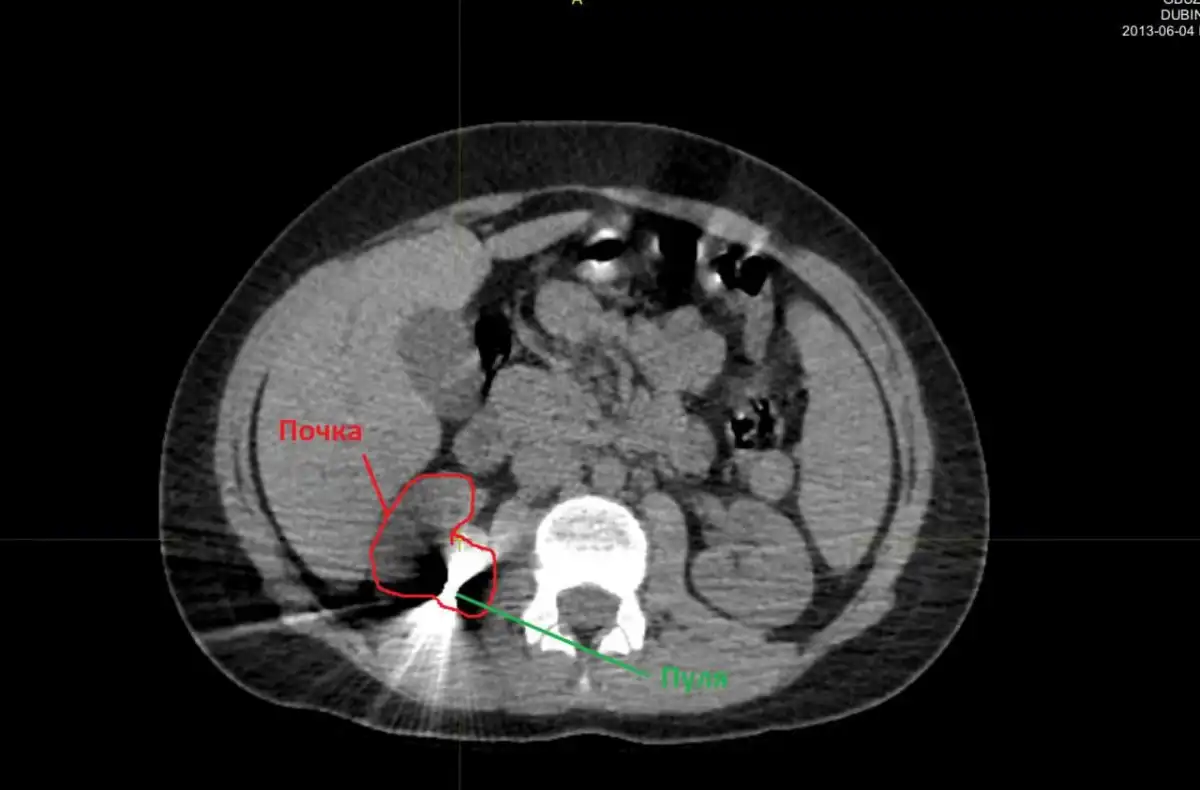

В детской областной больнице после тщательного обследования врачи выяснили, что пуля прошла через мягкие ткани и застряла в почке. Подросток прошёл курс лечения, и его состояние постепенно стабилизировалось. После чего было принято решение о проведении операции.

Операцию по извлечению инородного тела успешно провели хирурги Артём Вавилов и Ерануи Барсегян. Пуля была извлечена, а жизненно важный орган остался неповреждённым. Сейчас мальчик чувствует себя хорошо, находится дома среди родных и друзей.